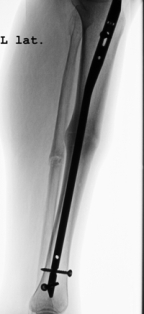

Abbildung 3 und 4: Ausheilung nach 1 Jahr. Das dünnere Wadenbein zeigt zu diesem Zeitpunkt nach keine vollständige Heilung, diese trat erst nach 18 Monaten ein.